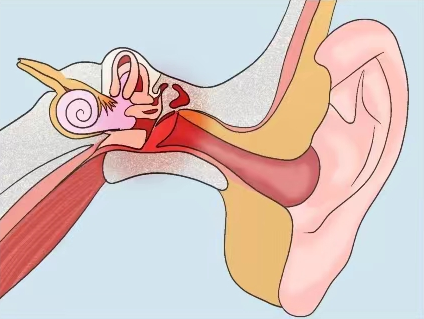

耳部手术

开展耳部手术,包括耳道良性肿物切除术、鼓膜修补术、鼓膜切开术置管术、鼓室成型术、乳突根治术等,用于治疗耳道良性肿物、外耳/中耳胆脂瘤,鼓膜穿孔、分泌性中耳炎、慢性中耳炎等耳部疾病。

分泌性中耳炎治疗成果展示

治疗前和治疗后

耳石复位技术

针对耳石症患者,根据体位试验确定耳石脱落位置并进行手法复位治疗,以及结合中医针灸治疗。患者的眩晕症状明显改善,并可减少复发。